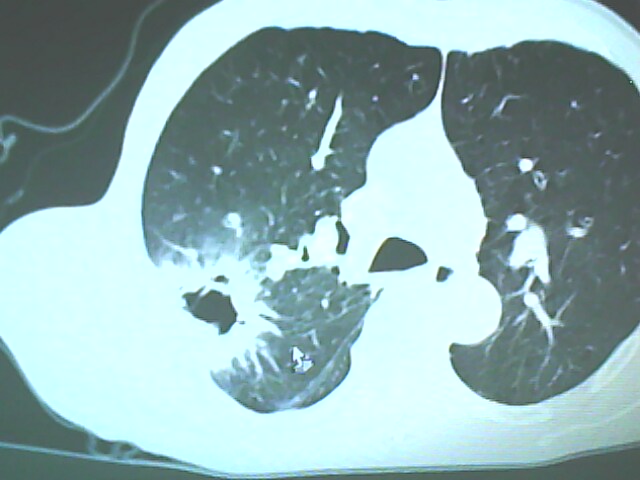

患者,男,66岁,以咳嗽、咳痰伴胸痛来就诊。

胸片提示右上肺占位病变。请各位老师看看ct。

考虑癌性空洞可能性大,空洞内壁不规则,病灶周围模糊,分叶、有毛刺

空洞内壁不规则,病灶周围模糊,分叶、毛刺呈日光放射状,突然截断,支持考虑癌性空洞

考虑右肺上叶后段周围型肺癌并癌性空洞形成。

考虑癌性空洞可能性大,内壁不规则,洞壁薄厚不均呈结节状突起,边缘模糊,分叶,毛刺

典型癌性空洞(偏心性,壁厚薄不均,内壁不光整),周围毛刺较僵硬,且有刺突征和血管聚集征